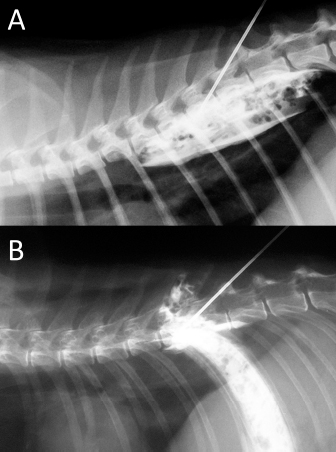

Fig. 6. NMB and ioversol mixed longitudinal and cloud-like (A) and intercostal (B) spread pattern in a lateral radiograph of a dog cadaver.

Although with some minor intra- and inter-specific differences, a positive air-LOR test was associated with longitudinal spread along the extrapleural compartment of the TPVS in 100% of the animals. In dog cadavers, the median injected volume (ml kg−1) of the mixture was 0.6 ml (0.22–1.25). The lateral thoracic radiographs showed multi-segmental spread in 100% of the subjects, with a median of 4.5 (2–10) vertebrae and a distribution of 2.5 (0–7) vertebra cranial and 1.0 (0–3) vertebra caudal to the injection level. A longitudinal spread pattern was noted on all radiographs, mixed with a cloudy pattern in 11/14 (78%) images and with an intercostal pattern at the level of the ninth intercostal space in 1/14 (7%) image (Fig. 6). Necropsy revealed multi-segmental ipsilateral longitudinal spread in 100% of the subjects (Fig. 7). The median stained intercostal spaces were 6.5 (4–11), with 5 or more spaces stained in 78%, whereas contralateral longitudinal spread was detected in 9/14 (64.3%) spaces, with a median of 2.5 (0–6) (Fig. 8). The median cranial versus caudal spread ipsilateral and contralateral to the injection site was 3 (1–7) versus 2 (0–3) and 0 (0–4) versus 1 (0–2) space, respectively. Distributions of NMB and ioversol after each mixture injection are shown in Figure 9. The only statistically significant correlation was between the radiographical and the necroscopic assessment of the longitudinal spread in the dog cadavers ( p=0.0028).